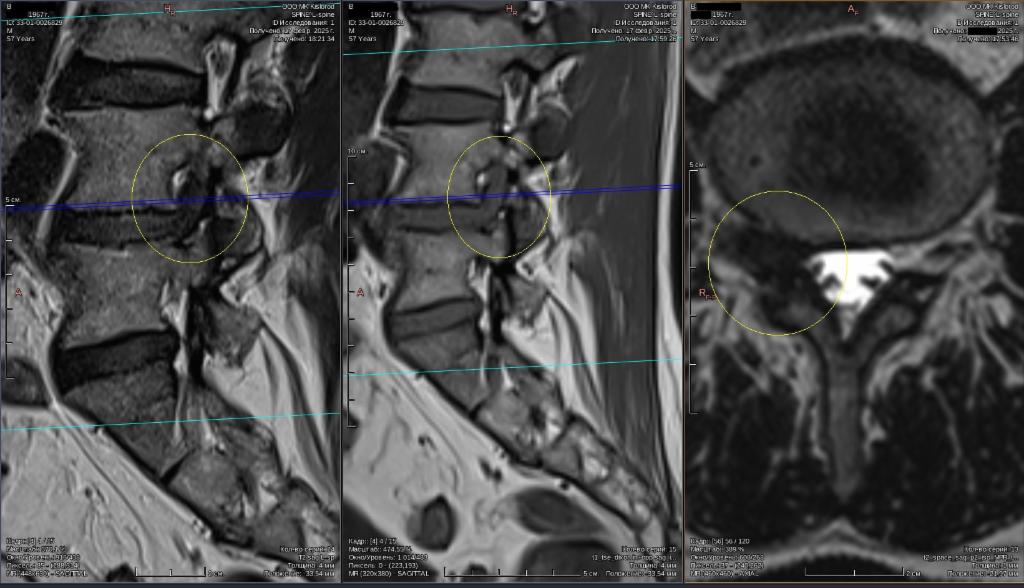

Грыжа Диска L5 S1 Фото

Грыжа Диска L5 S1 Фото 108 фотографий